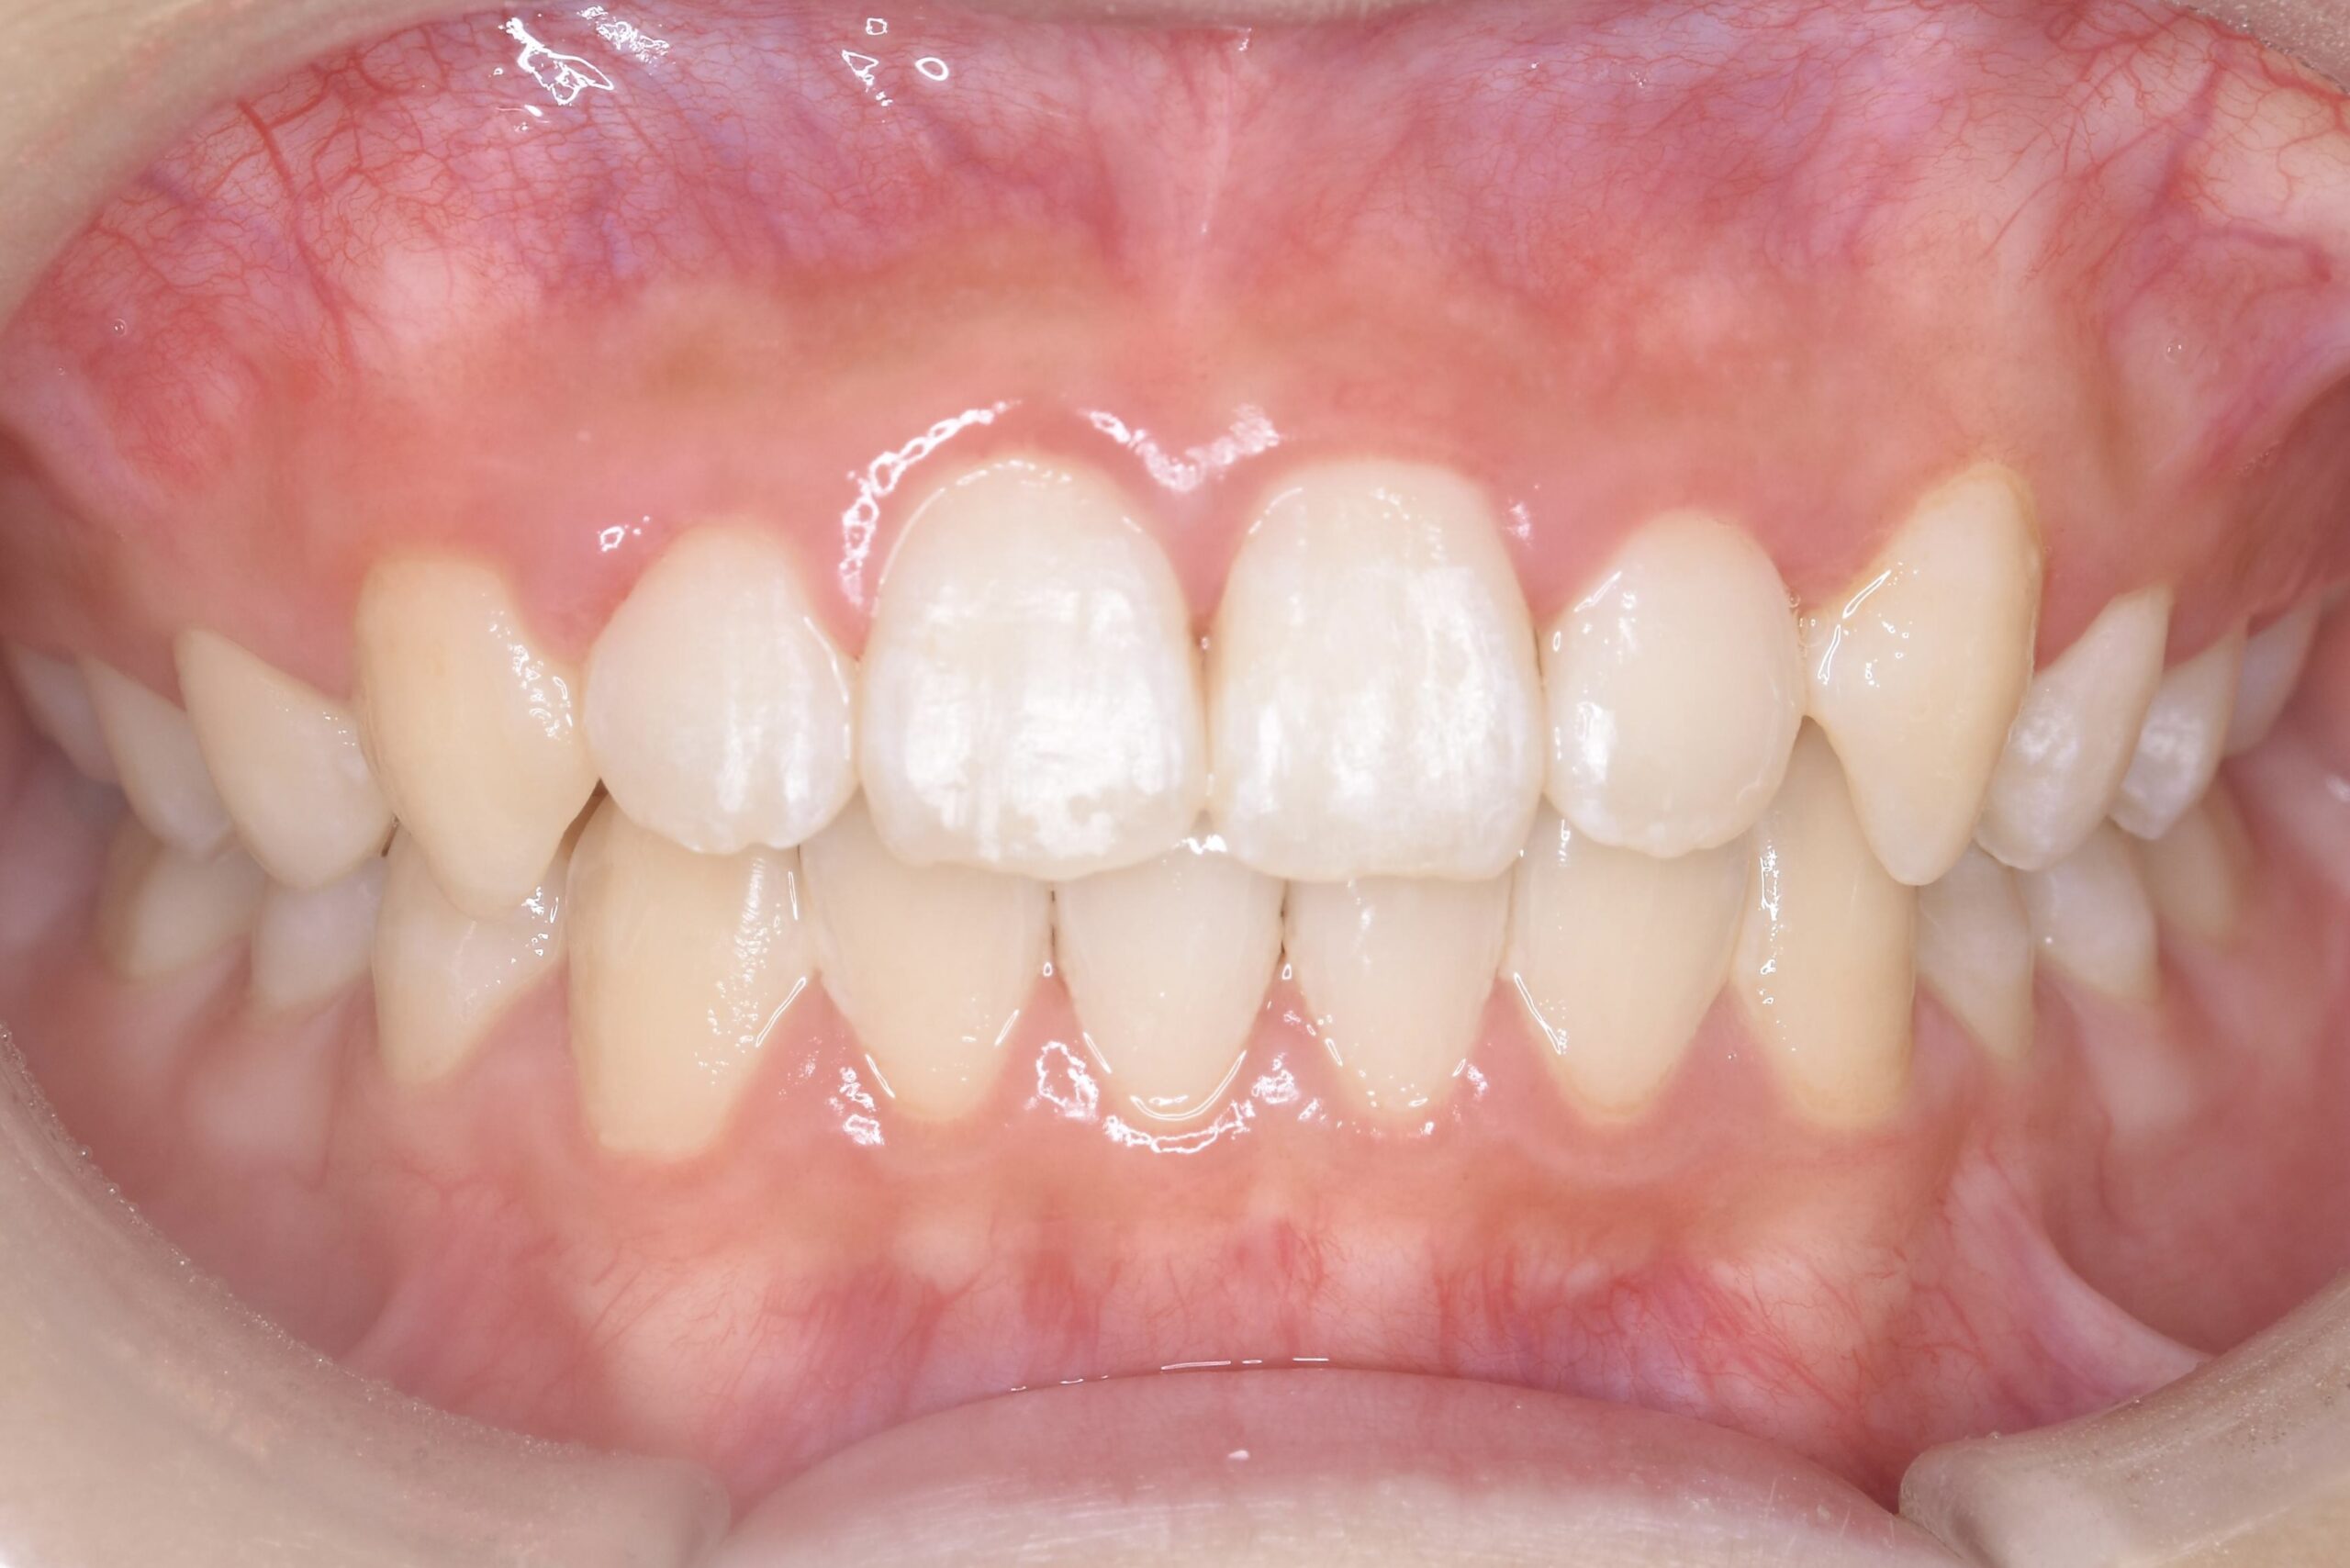

歯が生え揃う12歳頃〜成人後も

永久歯が生え揃ってから行う矯正歯科治療です。

患者様それぞれのご希望を叶えられるよう、難症例にも対応できる装置はもちろん、治療中の見た目を気にされている方も安心できる、透明で目立たないマウスピース型矯正装置もご用意しております。